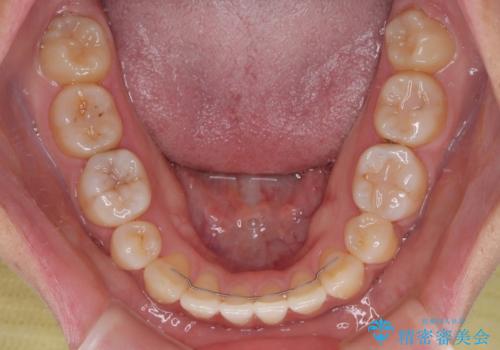

- 下顎小臼歯が欠損しており、さらに上顎が全体的に突出していることを気にして来院された患者様です。

下顎は片方の小臼歯が欠損していたため、正中がずれた上に、上下前歯が接触していない状態でした。

上顎左右の小臼歯2本および下顎小臼歯を1本抜歯し、補助装置を用いて上顎大臼歯が前方に移動しないように固定した上で、ワイヤー装置にて矯正治療を行うこととしました。

上下前歯のズレは舌の突出癖による影響も大きいと考えられたたため、舌のトレーニングをしっかりと行っていただきました。